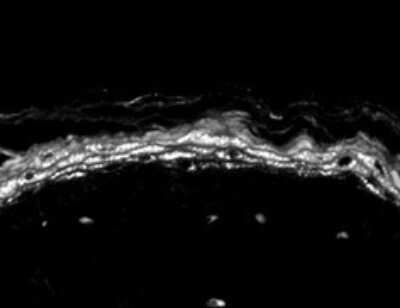

Immunohistochemistry: Nav1.8 Antibody (S134) [NBP1-47615]

Immunohistochemistry: Nav1.8 Antibody (S134) [NBP1-47615] - Mouse backskin sections. Courtesy of Dr. Turksen, Ottawa Hospital Research Institute, Canada.